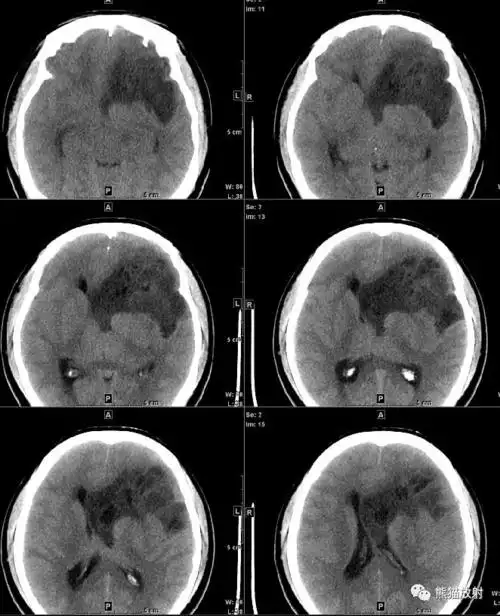

读片丨女30岁间断性头痛颅脑ctmri